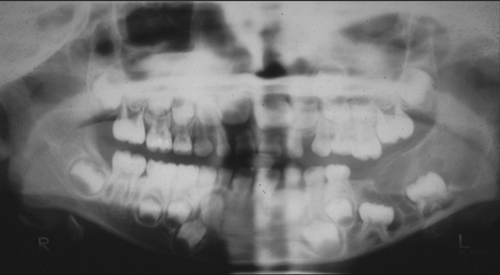

Clinical information The patient was a 6 year-old boy. He was brought to his pediatrician because of a painless mandibular expansion on his left side. His pediatrician noted a smooth expansion in his left mandible and at the same time the first molar has not erupted over the expansion. The patient was referred to the clinic of a local dental school for treatment. On physical examination, the patient was afebrile. Development of his face and skull appear to be within normal limits except for the aforementioned expansion. There was no sign of dental infection or sinus drainage site. A panoramic view was taken and demonstrated a well defined multilocular lesion that involves the molar ramus of the left side of his mandible. The lesion was excised. The followings are representative images.

The panoramic view demonstrated a mulilocular lesion in the left ramus of the mandible. The lesion is well defined and without much sclerotic changes at the rim. The first molar is unerupted and is associated with the lesion (arrow in Panel A). On histologic section, the lesion is composed of a solid mass with numerous thin, anastomosing trabecula or cords of epithelial cells. At the and of these branching anastomosis, there the epithelial component tend to expand a little and form a small island. No larger islands are noted (Panel B and C). No calcification or eosinophilic depositions are noted in the epithelial islands. There is no microcyst formation in the epithelial component and the overall pleomophism is minimal . The embedding stroma is composed of a moderately cellular, stellate shaped, rather monotonous proliferation of cells without high grade nuclear features nor mitosis.